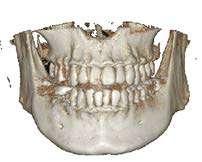

Figuras 3 y 4 . Corte del Cone-beam dental tras la exodoncia y regeneración del alveolo con Endoret-PRGF cuatro semanas después. Podemos observar la atrofia ósea en sentido vertical de la zona con una altura máxima de 3 mm. La planificación como podemos visualizar será para la realización de una elevación transcrestal mínima y la colocación de un implante extracorto.

Figura 12. Mantenimiento de la altura ósea lograda y de la estabilidad del implante al año de carga visualizada en cone-beam.